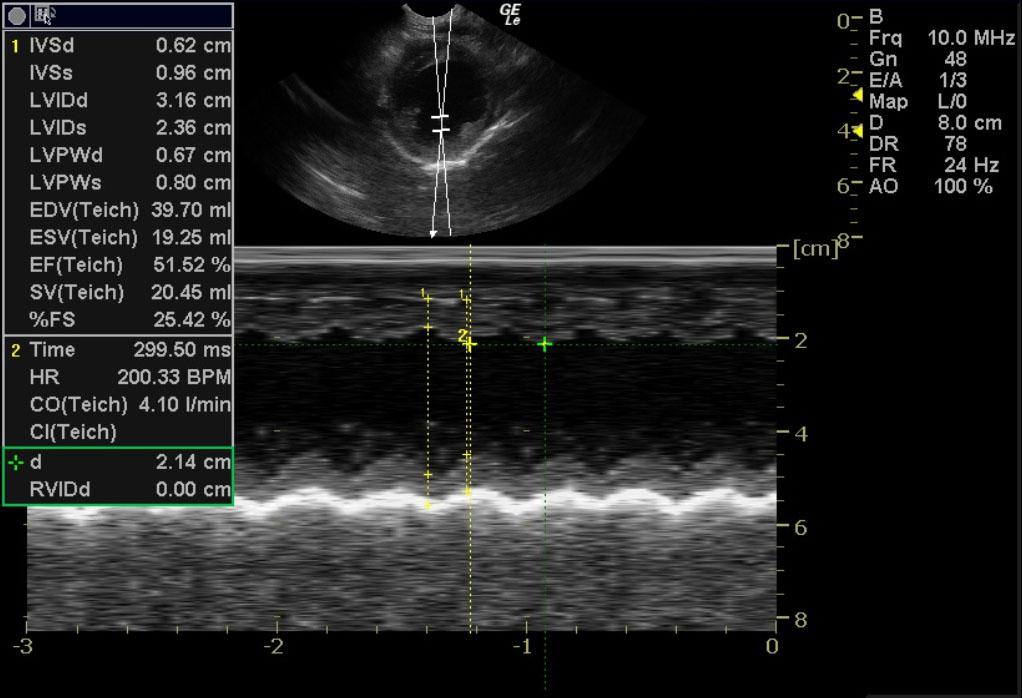

A one month old sheltie cross dog with a history of 5 of 7 littermates dying from parvovirus was presented for lethargy, and diarrhea. Parvovirus was identified in a littermate’s myocardium at necropsy.